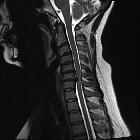

length, and enhancement: systematic approach to differentiating intramedullary spinal cord lesions. Compressive myelopathy. A 50-year-old patient with bilateral hand tingling. a Sagittal T2 image shows severe spinal canal narrowing at C3–C4 due to degenerative changes, with focal faint signal hyperintensity (arrow). b Post-contrast image shows focal enhancement (arrow)